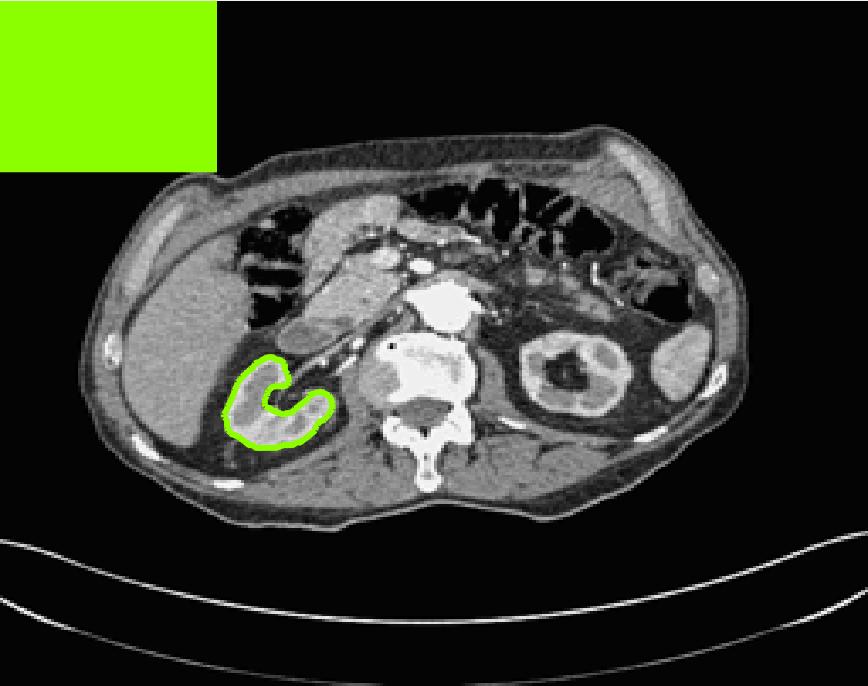

Test Images. We will perform initial tests on the images shown in Figs. 5–7. We have provided the ground truth and initialisation used for each image. Test Images 1–3 are synthetic, Test Image 4 is an MRI scan of a knee, Test Images 5–6 are abdominal CT scans, and Test Images 7–9 are lung CT scans. They have been selected to present challenges relevant to the discussion in §2. We focus on medical images as this is the application of most interest to our work. In the following we will discuss the results in terms of synthetic images (1–3) and real images (4–9). We also test the proposed approach on a larger data set of 30 CT images (a sample of which is presented in Fig. 18), comparing against existing selective methods detailed in §3.

Real Images. In Fig 12 we present results for Test Images 4–6. Here, the proposed model performs in a similar way to its competitors because these images are more typical selective segmentation problems in the sense that there is a clear distinction between the foreground and background intensities. In particular, the values in each case are: Test Image 4 , Test Image 5 , and Test Image 6 . It can be seen that the proposed model is competitive compared to previous approaches. The performance is quite poor for Test Image 5, but is arguably still the best for this challenging case. In Fig. 13 we present results for Test Images 7–9. Here the proposed model outperforms previous approaches significantly for each image. This is mainly due to the type of image considered. Specifically, the true intensities are: Test Image 7 , Test Image 8 , and Test Image 9 . The proposed model is capable of achieving results where , with other models failing completely in these cases.

7.4 Alternative Selective Methods

In order to further establish the robustness of our method, we now introduce the results of testing our approach against competing interactive segmentation methods on a larger data set. The results are presented in Fig. 17, showing a boxplot of accuracy in terms of TC on a set of 30 CT images (excluding outliers). The target structure we consider is the spleen, as this consists of a relatively homogeneous foreground, appropriate for the approach considered. The data has been manually contoured providing ground truth data for the image set. We compare CAC Nguyen:12 and SRW SRW against our method with five variations of user input for each image. It is worth emphasising here that the input used in the tests is identical for each approach and was not refined in any way. It was designed to mimic what a user, unfamiliar with each approach, might select intuitively. A representative example for three images is shown in Fig. 18. This shows foreground (red) and background (blue) user input regions. For our method, we define the red region as as discussed in §1 and enforce hard constraints on the blue region. We refer to the results of the proposed approach using this input as Ours (i). We also include results of randomising the user input in an identical way to §7.3. For each image we generate 1000 simulated user input choices, which we present as Ours (ii). It is important to note that the difference between Ours (i) and (ii) is only the definition of . The method and parameters are fixed between each.